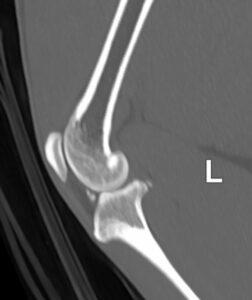

X-ray – Left Stifle

Diagnostics: Odysseus was admitted for CT and joint taps under general anaesthesia. He was sedated with the owner to reduce the stress associated with the procedure. On CT, he had bilateral intra-articular lesions possibly associated with a cranial cruciate ligament disease and historic fractures of his right metatarsals with callus formation. There were some mild osteoarthritic changes in some joints but his spine was normal. Joint taps showed changes that could indicate IMPA but this was not definitive.